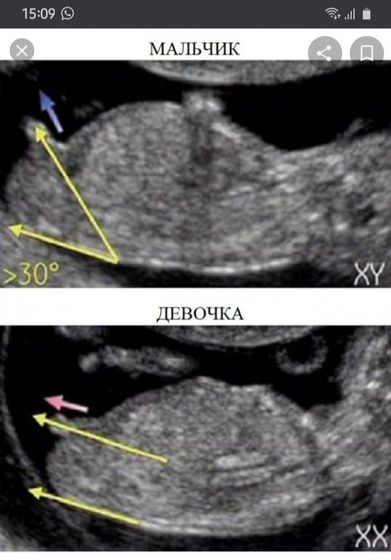

Пол ребёнка на узи)

Глупо конечно гадать, но мало ли) раз все скидывают)

1 фото из интернета, второе моё)